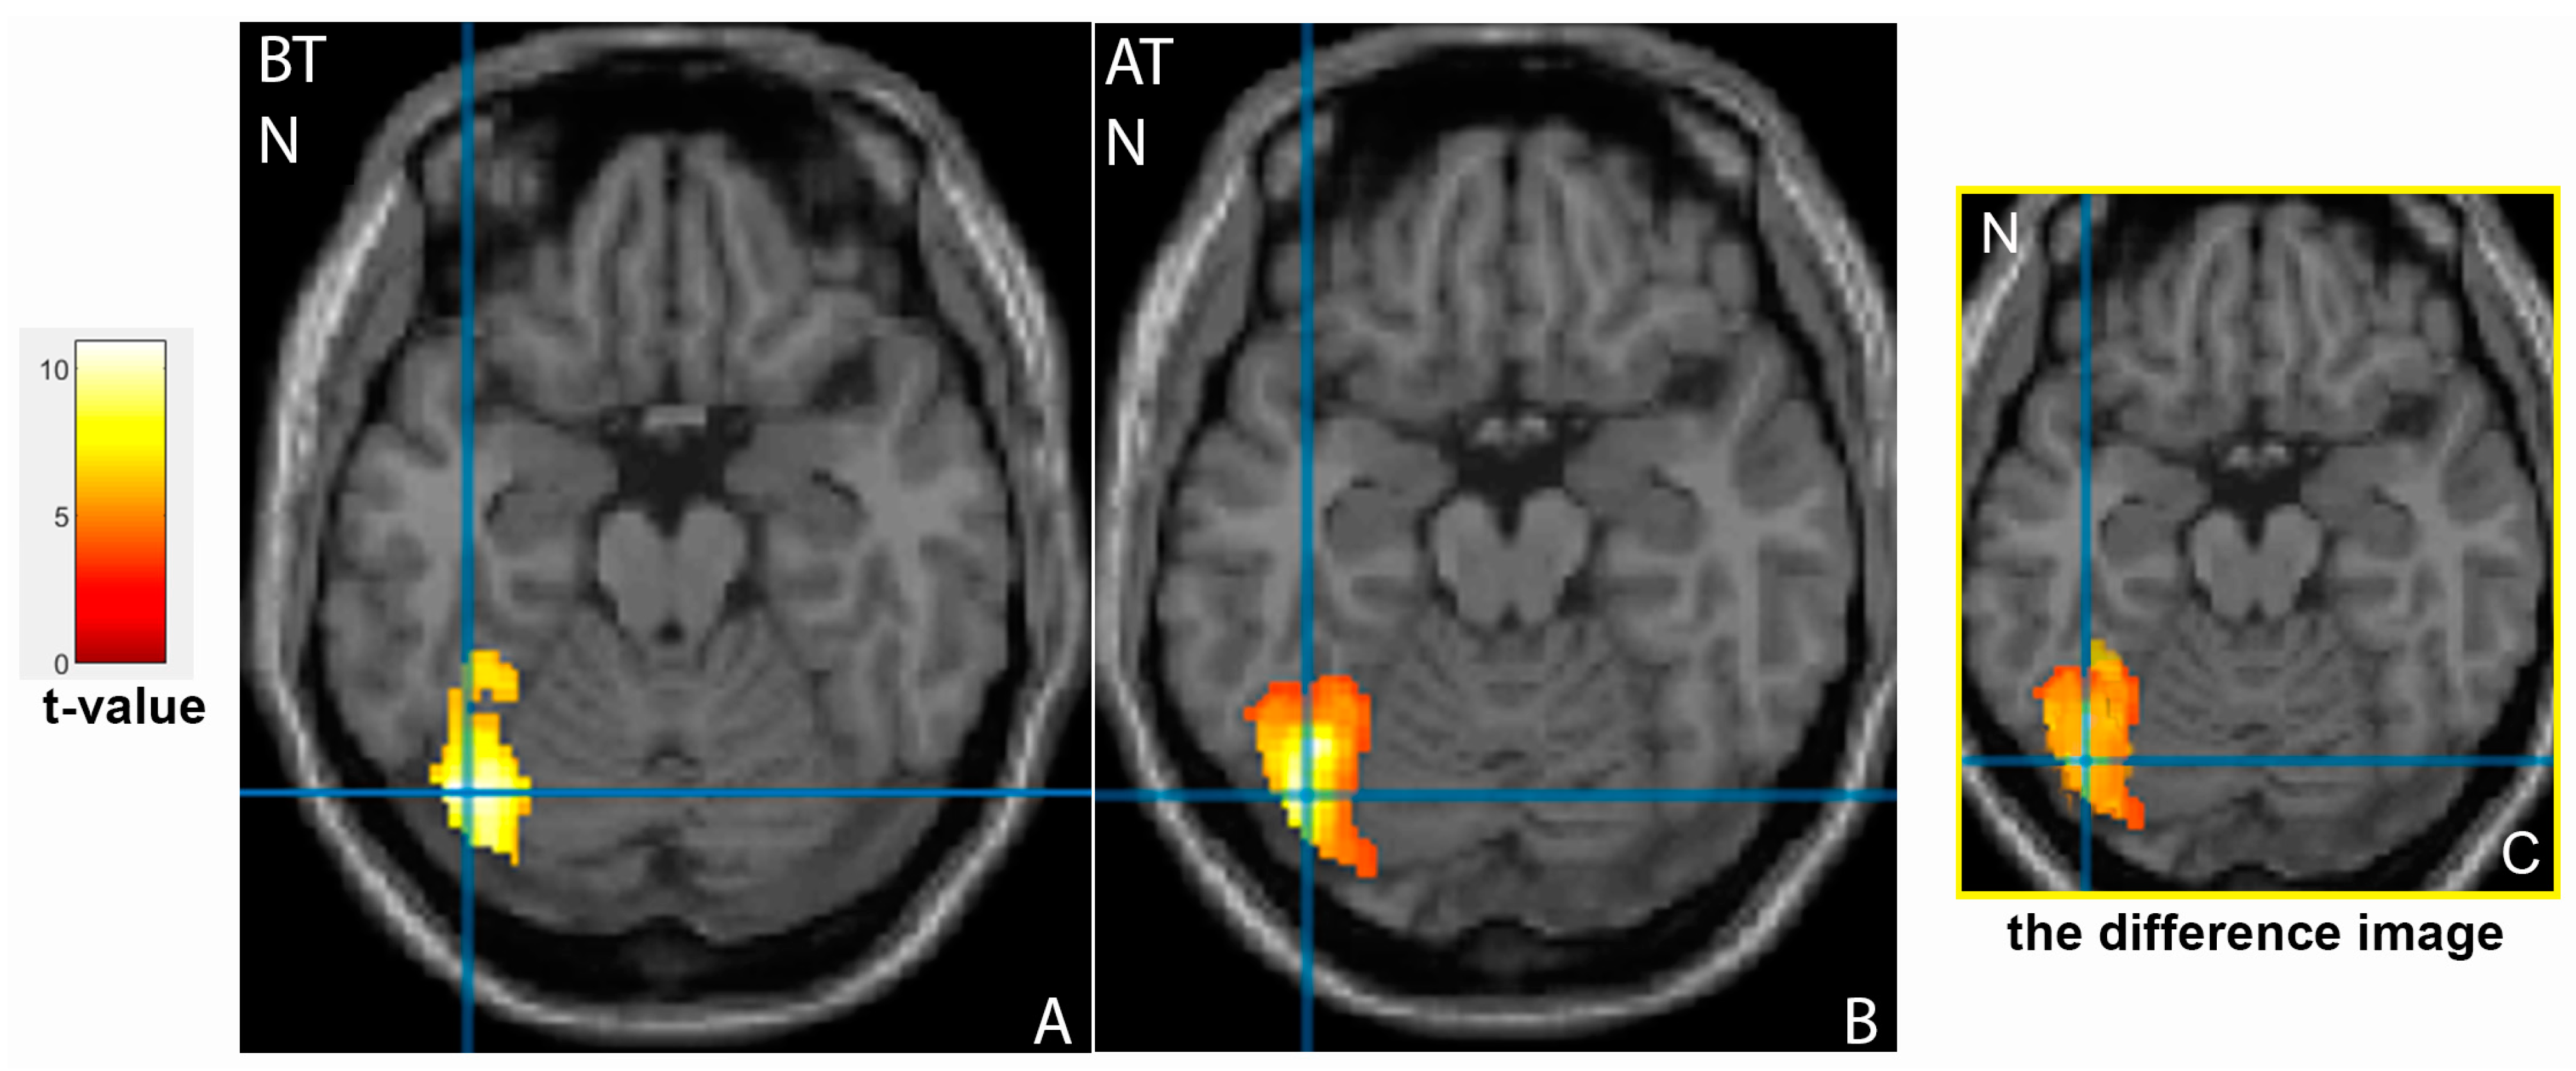

3.2. Comparison of Brain Activation Patterns in Patients before and after Treatment

| Cluster Location | Emotion | Extent | t-Value | p (FWE Corrected) | MNI Coordinates |

|---|---|---|---|---|---|

| Patients group before therapy | |||||

| Frontal cortex | |||||

| Left middle frontal gyrus, BA46 | N | 1457 | 6.24 | <0.001 | −48;38;20 |

| Right inferior frontal gyrus, BA46 | N | 632 | 8.83 | 0.001 | 50;40;4 |

| Right middle frontal gyrus | N- | 2064 | 10.89 | <0.001 | 54;20;30 |

| Right inferior frontal gyrus | P+ | 2368 | 8.91 | <0.001 | 46;22;8 |

| Patients group after therapy | |||||

| Right inferior frontal gyrus | N | 1390 | 10.97 | <0.001 | 38;4;28 |

| Right middle frontal gyrus | N- | 386 | 5.51 | 0.008 | 46;30;26 |

| Occipital cortex | |||||

| Left fusiform gyrus, BA37 | N | 1532 | 6.48 | <0.001 | −40;−68;−20 |

| Right fusiform gyrus, BA37 | N | 1861 | 7.44 | <0.001 | 44;−58;−24 |

| Temporal cortex | |||||

| Left superior temporal gyrus, BA22 | N- | 420 | 5.94 | 0.005 | −48;12;−4 |